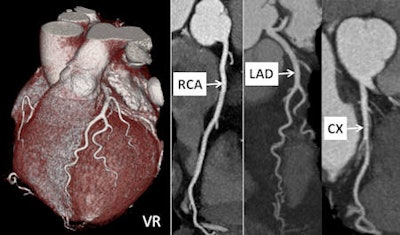

CT coronary artery calcification (CT CAC) is proving effective for triaging patients who have presented at the rapid access chest pain clinic in a leading U.K. hospital. Based on six years of experience, the technique may now be more useful than traditional assessment methods.

Initial evaluation of patients with nonacute chest pain has traditionally involved calculation of pretest probability, consideration of cardiovascular risk factors, resting 12-lead ECG, and an exercise treadmill test before further stress imaging or invasive coronary angiography. However, the U.K. National Institute for Health and Clinical Excellence (NICE) published guidelines last year, and they recommended using CT CAC as a first-line diagnostic tool in stable chest pain patients with a pretest probability (PTP) of between 10% and 29%.

"CT CAC is a low radiation dose and relatively inexpensive technique that can be provided as a rapid service in busy imaging departments," noted authors from the Chest Pain Clinic at Harefield Hospital in Harefield, U.K., in a poster presentation at the European Society of Cardiology (ESC) 2011 annual congress in Paris.